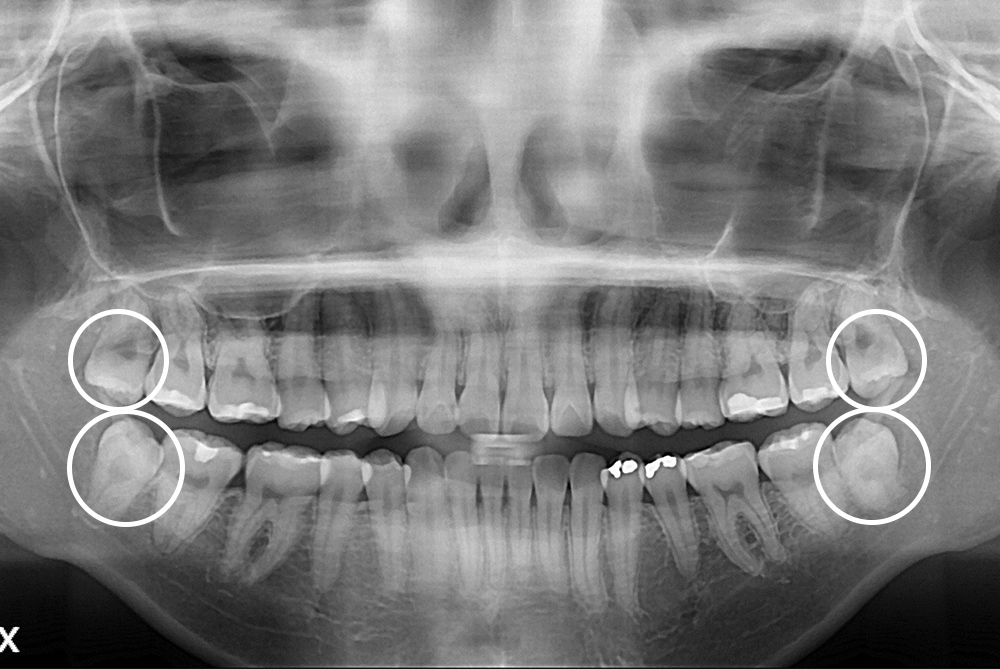

[사랑니] 매복 사랑니 발치

치료후 : 2020-01-15

세종치과는 구강악안면외과학 박사이신 원장님이 발치하는 치과입니다.